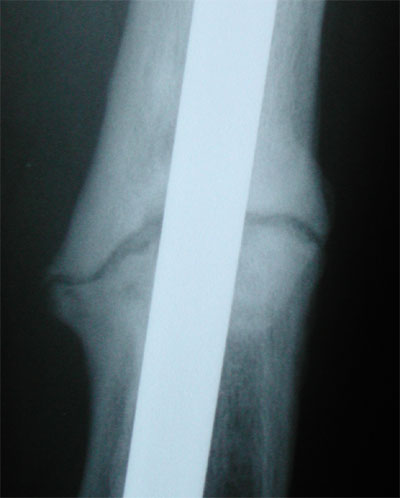

June 30, 2005 X-ray update

Again, things are feeling better, and this time the doctor even thinks he sees signs of progress, slow that it is. Left image is May 5, and on the right is June 30. The gaps are not changing much from the front view, but you can see where the space in between looks like is has more bone showing through. See the Lateral View to see what is happening there.